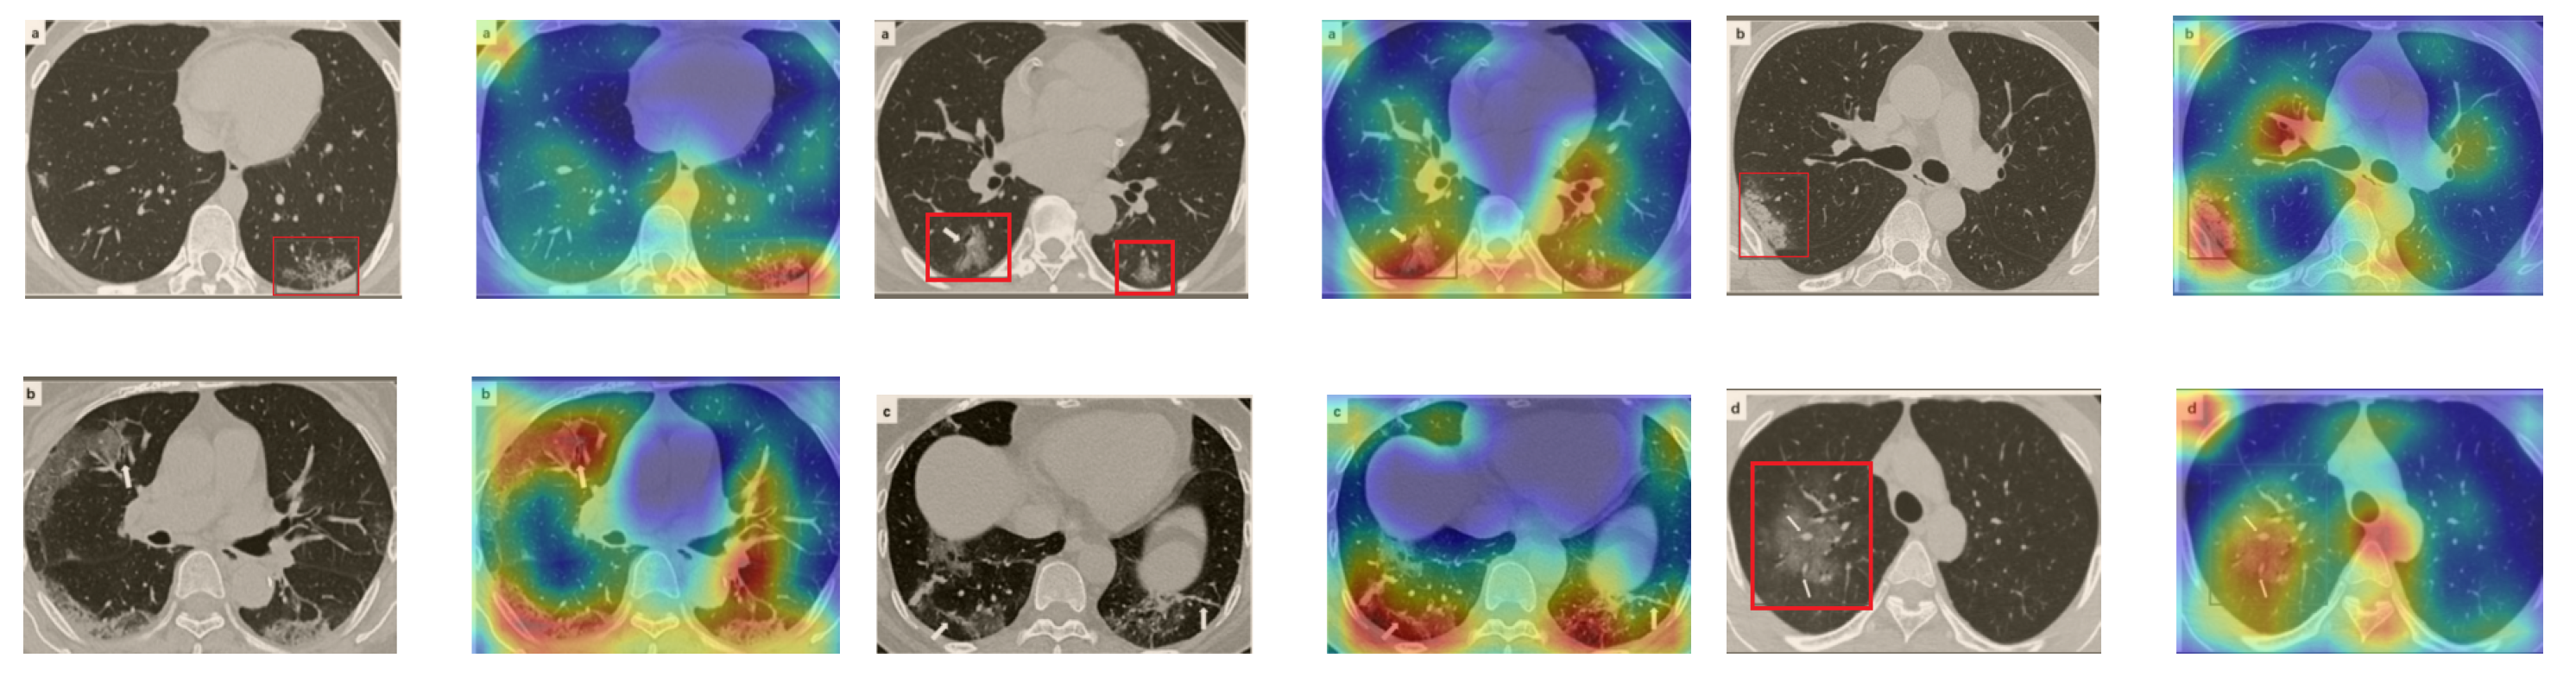

In a similar way, we considered classifying the test CT scans from the COVID-19 dataset by the DenseNet169 model, and highlight the important regions considered for predictions. We present samples of CT images and their localization maps in Figure 14. We can also see that our model is capable of detecting the COVID-19-related regions as annotated (small square in some images) by expert radiologists.

Figure 14.

Grad-CAM visualizations for sample CT images from the COVID19-CT dataset. Our DenseNet169 model correctly classified them as COVID-19 cases and highlighted the most relevant regions, as shown in the corresponding localization maps.